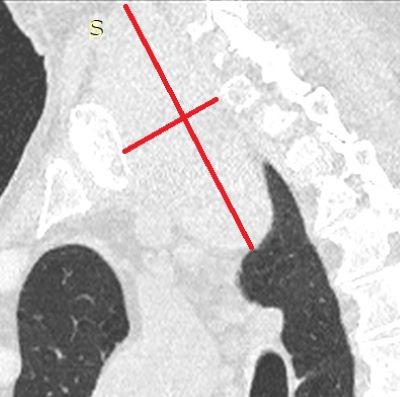

После выполнения МСКТ органов грудной полости на полученных изображениях была выявлена увеличенная правая доля щитовидной железы.

Увеличение правой доли щитовидной железы, с наличием диффузных кальцинатов в структуре.